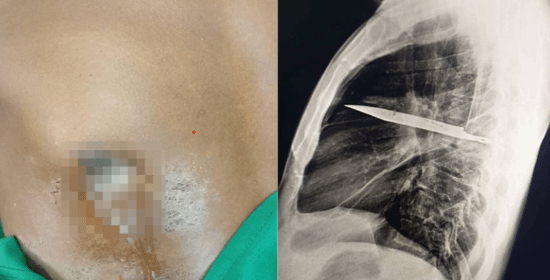

• 男子胸部流膿 X光發現刀留體內8年:剛好避開心臟血管

近日,坦桑尼亞出現一起罕見醫療案例,一名44歲男子右側乳頭附近長期流出惡臭膿液,情況反復無法改善,因而前往就醫。醫療團隊初步檢查發現,他的下方確實持續排出膿液,周圍組織也變硬,但男子本身沒有胸痛、咳